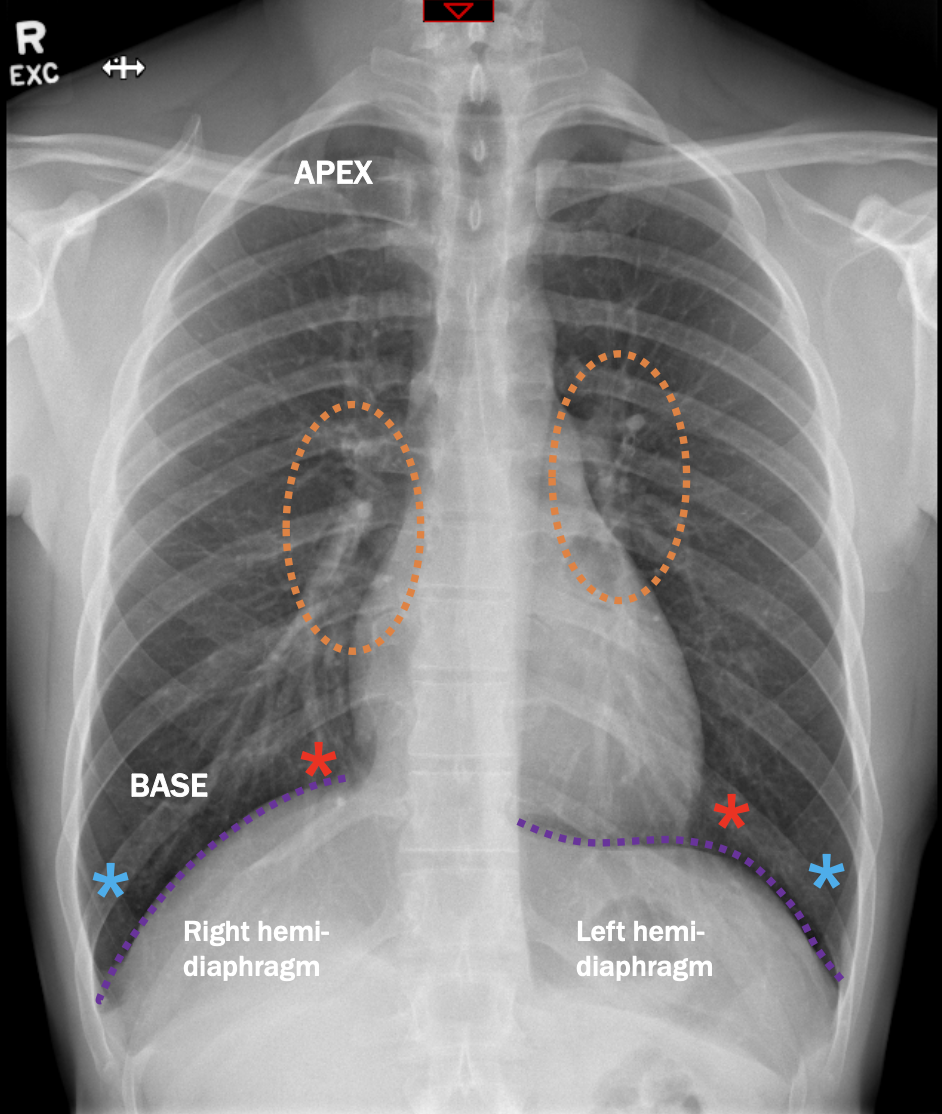

What anatomy is labelled with the blue asterisk?

costophrenic angles

What anatomy is labelled with the red asterisk?

cardiophrenic angles

What anatomy is labelled with the orange circles?

Hilum